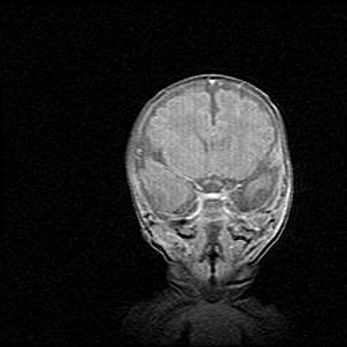

Церебральная ишемия II.

Возраст: 5 дней

Вес: 3400 г

Пол: женский

Окружность головы: 35 см

Срок гестации: 39 недель

Церебральная ишемия – это заболевание, характеризующееся недостаточностью (гипоксией) либо полным прекращением (аноксией) снабжения мозга кислородом по причине закупорки одного или нескольких сосудов. Это приводит к  что метаболическим расстройствам различной степени тяжести в тканях головного мозга, развитию коагуляционных некрозов и гибели нейронов.